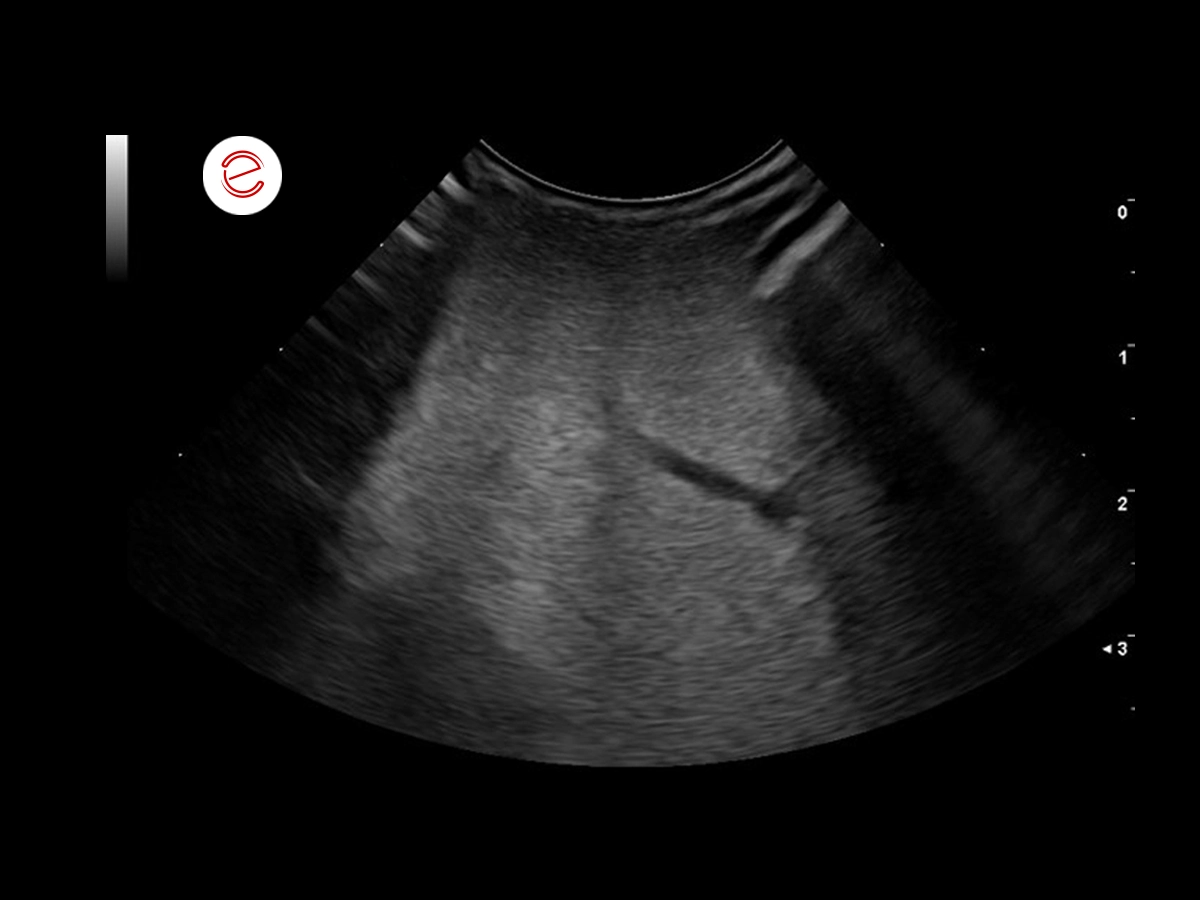

In this case, a hyperechoic oval structure was visible in the lateral wall of the left ventricle.

Measurement of the mass within the myocardium of the left ventricle.

Differential diagnoses include a granuloma (fungal or bacterial), neoplasia and hematoma.